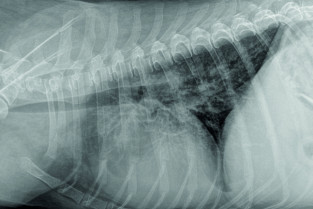

Pneumologie

- interpréter les radiographies du thorax ;